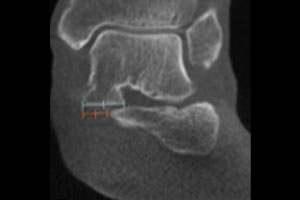

A 58-year-old patient with significant ankle pain sought a consultation with Dr. Walther. The patient had seen several orthopedic surgeons, one of whom had prescribed orthotics. However, the orthotics did not alleviate her pain. Her supine medical CT (MDCT) scan denoted only minimal arthritis. The patient could not get an MRI due to her pacemaker. Dr. Walther ordered a weight bearing CT (WBCT) scan, which revealed significantly reduced joint space. He performed a successful total ankle replacement on the patient three months later.

“A WBCT exam of the ankle joint and the foot allows a completely new evaluation of many deformities. It allows axis misalignments, joint instabilities, or osteoarthritis to be better classified.”